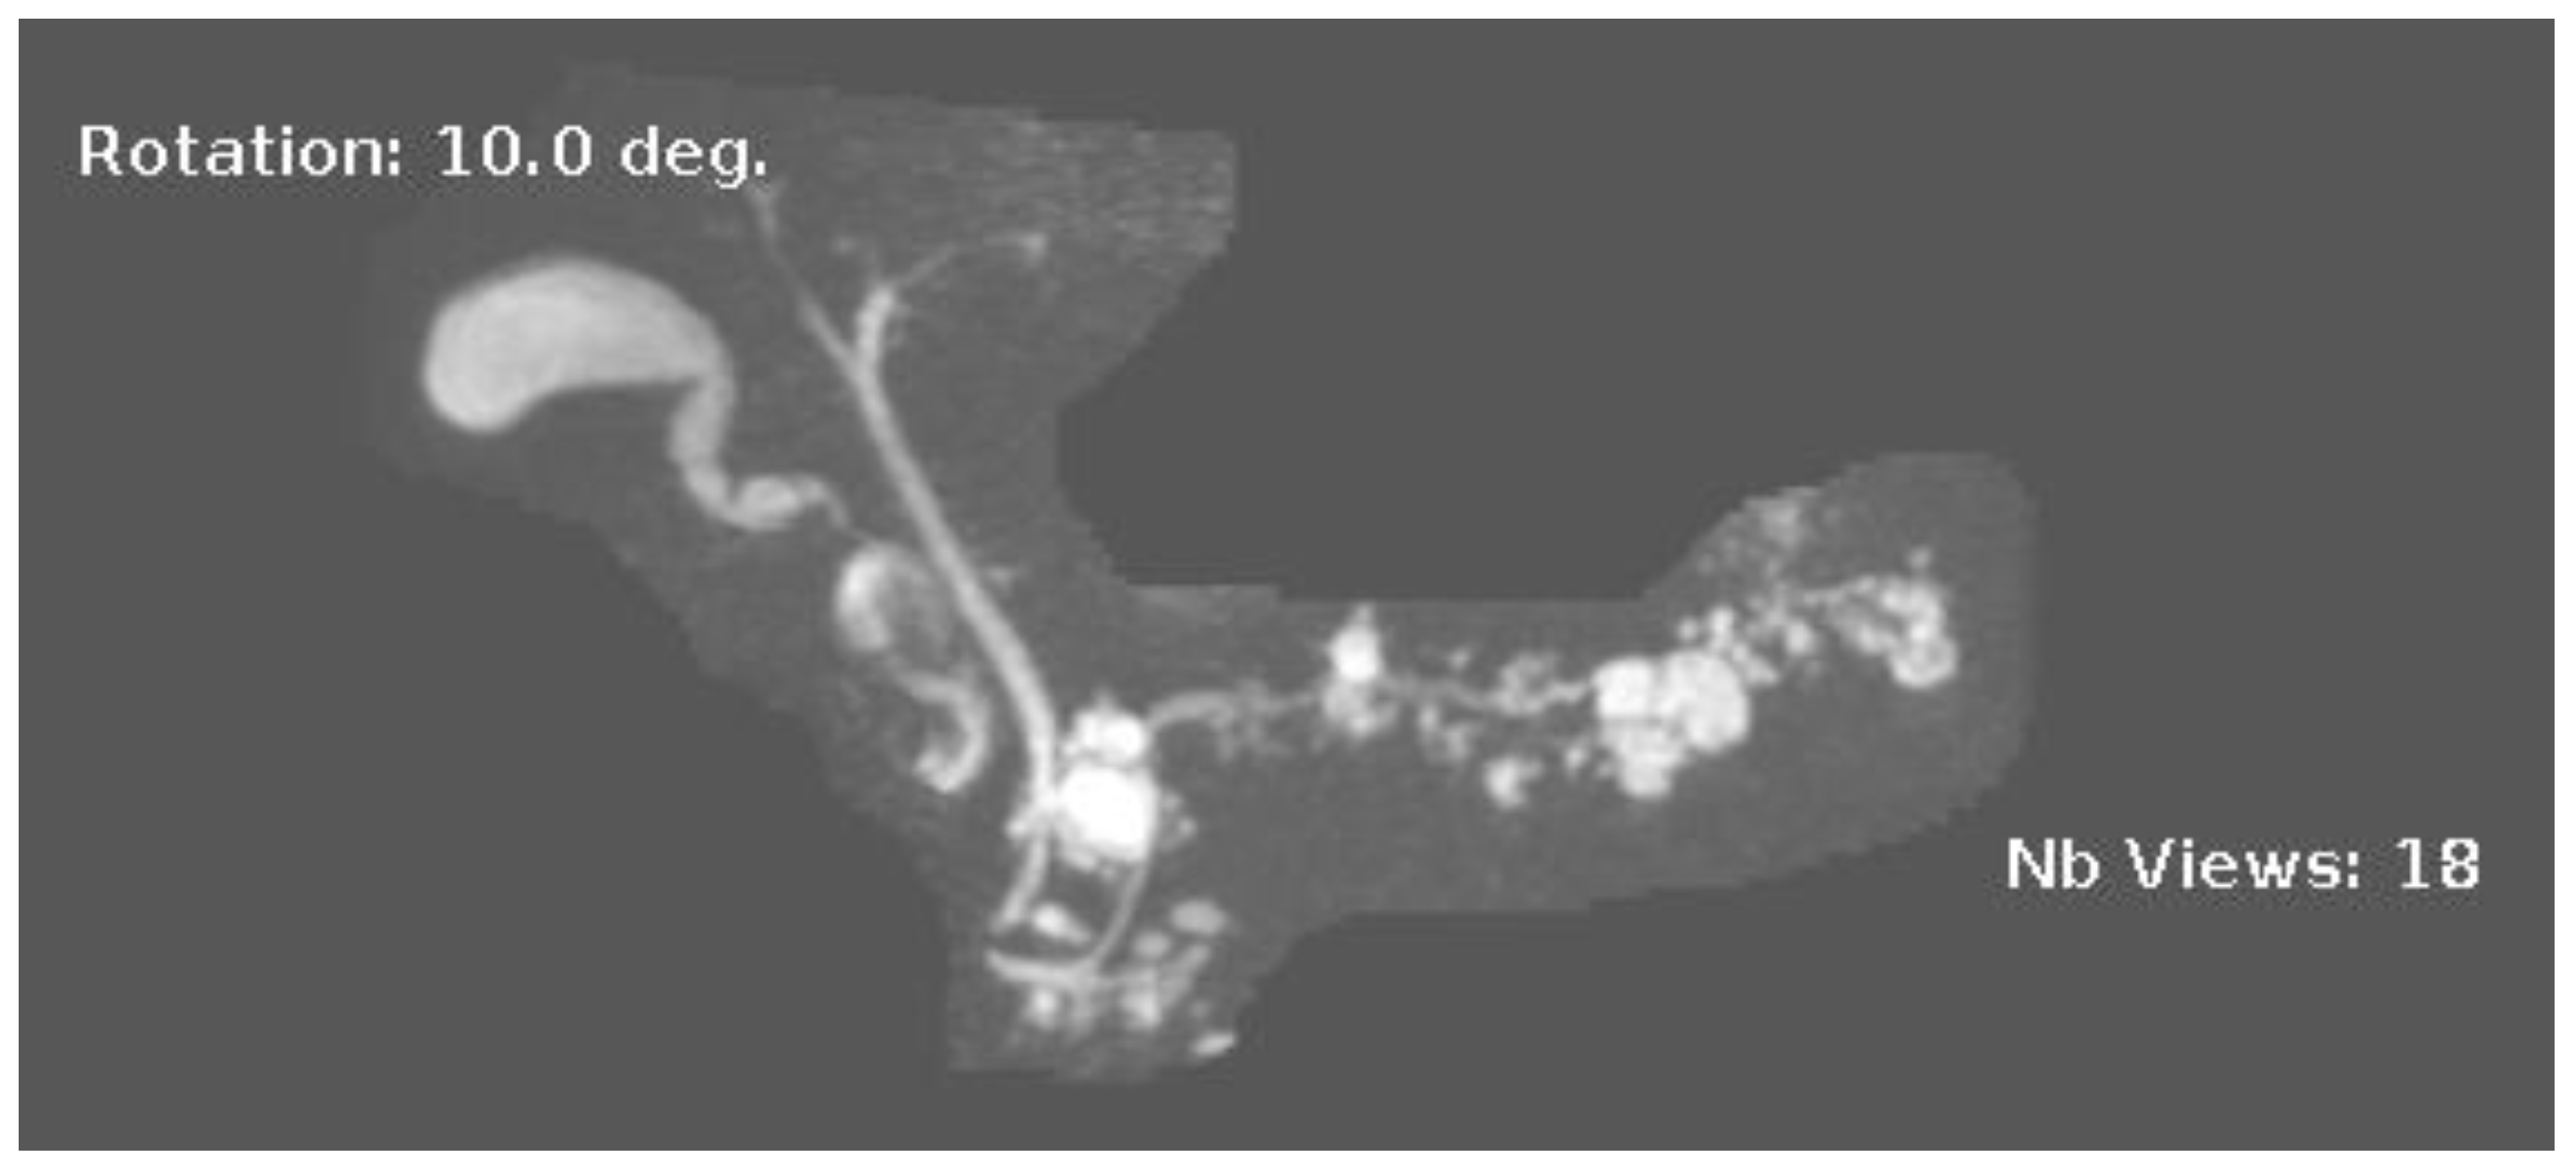

Figure 3.

MRI image of side branch IPMN.

IPMNs can be divided into main duct intraductal papillary mucinous neoplasm and branch duct intraductal papillary mucinous neoplasms, with dilation of the main pancreatic duct helping to distinguish between the two. They usually present in the fifth to seventh decade of life and have an equal distribution between males and females [15]. Intraductal neoplasms are typically associated with a dilated main pancreatic duct (Figure 2a,b), whereas the branch duct IPMNs are associated with a dilated pancreatic duct branch or branches (Figure 3). A mixed IPMN is defined as a cystic lesion with ductal communication and main pancreatic duct dilation greater than or equal to 5 mm (Figure 4). Diabetes mellitus (DM) and a family history of pancreatic adenocarcinoma are known risk factors for IPMN, with odds ratios of 1.79 (CI 95%: 1.08–2.98) and 2.94 (CI 95%: 1.17–7.39), respectively [16]. Cytology can show columnar cells with variable atypia and can stain positive for mucin. CEA is usually greater than 200 ng/mL in approximately 75% of lesions, similar to mucinous neoplasms. Main duct IPMNs have a 36–100% risk of malignant potential, compared to a lower risk of 11–30% malignant potential of side branch IPMNs [17].